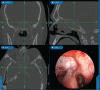

Background: Chronic rhinosinusitis (CRS) is one of the most common chronic medical conditions, with a significant impact on patient quality of life. CRS is broadly classified into two groups: CRS with nasal polyposis (CRSwNP) and CRS without NP (CRSsNP). Clinically, the major subtypes of CRSwNP may be divided into eosinophilic chronic rhinosinusitis (e.g., allergic fungal rhinosinusitis and aspirin-exacerbated respiratory disease [AERD]) and nasal polyps associated with neutrophilic inflammation (e.g., cystic fibrosis [CF]). CF is characterized by mutation of the gene encoding the CF transmembrane conductance regulator. Functional endoscopic sinus surgery is usually required for most NP patients with increased frequency in patients with AERD. This study provides a review of the epidemiology and major classification of CRSwNP.